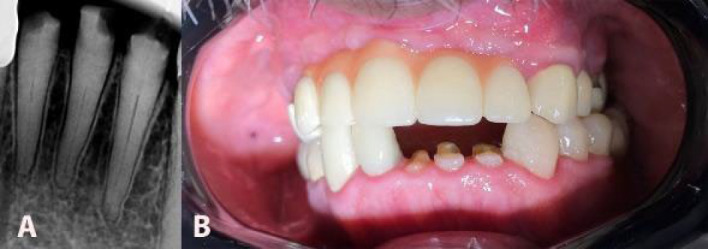

美国牙髓学协会将髓管闭塞(PCO)病例的处理列为高风险困难。这种分类表明程序错误的可能性增加了。然而,牙科技术的进步简化了钙化牙齿的牙髓治疗。引导牙髓学使用锥形束计算机断层扫描(CBCT)和三维(3D)打印机来创建针对患者的指南,提高了复杂病例的准确性和可预测性。一名健康的60岁男性由一名修复医生转介对23号、24号和25号牙齿进行根管治疗。根尖周x线检查显示所有牙齿均有部分PCO。选择牙髓治疗后,利用CBCT成像和口腔内3D扫描设计患者特异性牙髓治疗指南。在验证了内导器的稳定性后,使用Munce Discovery钻头制备了通道腔。在运河协商之后,确定了工作长度。根管治疗使用25/0.04%旋转锉和次氯酸钠冲洗。采用热冷凝技术完成封闭。虽然PCO存在,但治疗过程中未发生并发症。牙齿保持完全无症状和功能,表明治疗成功。引导牙髓治疗是治疗下颌骨PCO的一种实用且可预测的方法。该技术提供了准确的根管定位,减少了程序错误,并保留了牙齿结构。尽管担心成本、辐射暴露和解剖学变异的挑战,但它代表了根管治疗的一个有希望的进步。

The American Association of Endodontics classifies the management of pulp canal obliteration (PCO) cases as a high-risk difficulty. This classification indicates an increased likelihood of procedural errors. However, advancements in dental technology have simplified the endodontic treatment of calcified teeth. Guided endodontics uses cone-beam computed tomography (CBCT) and a three-dimensional (3D) printer to create a patient-specific guide, enhancing accuracy and predictability in complex cases. A healthy 60-year-old male was referred by a prosthodontist for root canal treatment on teeth #23, #24, and #25. Periapical radiographic examination revealed partial PCO in all teeth. After choosing guided endodontics treatment, CBCT imaging and intraoral 3D scanning were utilized to design a patient-specific endodontic guide. After verifying the stability of the endo-guide, access cavities were prepared using a Munce Discovery bur. Following the negotiation of the canals, the working length was determined. Root canal treatment was performed using rotary files up to size 25/0.04% and sodium hypochlorite irrigation. The obturation was completed using the warm condensation technique. Although PCO was present, no complications occurred during treatment. The teeth remained completely asymptomatic and functional, demonstrating the success of the treatment. Guided endodontics can be a practical and predictable approach for managing PCO in mandibular incisors. This technique provides accurate canal location, reduces procedural errors, and preserves tooth structure. Despite concerns about cost, radiation exposure, and challenges with anatomical variations, it represents a promising advancement in endodontic treatment.